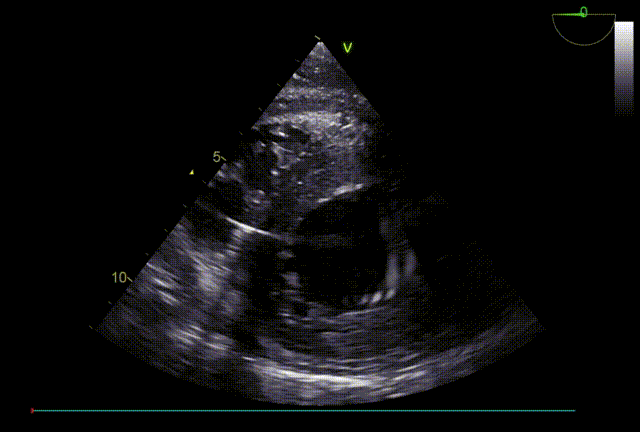

TTE入院

TTE